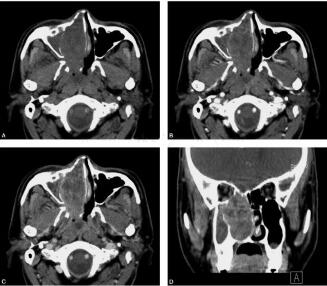

图1 鼻窦CT平扫、增强扫描及三维重组:图A、图B、图C为横断面平扫、增强早期及延迟期图像,图D为冠状面重建图像,图E、图F为横断面和冠状面骨窗。右鼻腔饱满,可见一软组织肿块影,内部密度相对均匀,边界清楚,形态欠规则,增强后可见不均匀中度强化;骨窗示周边未见明显骨质破坏,鼻中隔及右上颌窦内侧壁可见变薄、吸收及弧形移位

平扫见单侧鼻腔内肿块影,软组织密度,密度相对均匀,边界清楚,形态规则或不规则,周边骨质无破坏,多因肿块膨胀性生长而引起骨质吸收、变形,病变内部无钙化斑;增强扫描病变可见轻度不均匀强化。